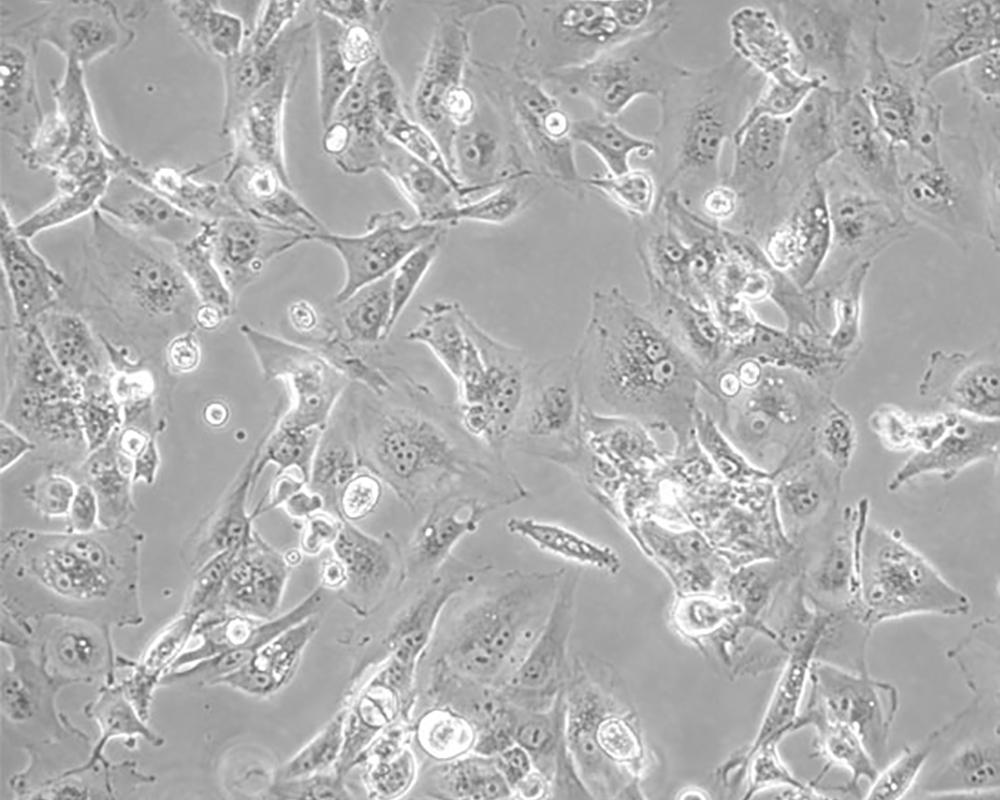

Caki-1

產(chǎn)品名稱 Caki-1

中文名稱 人腎透明細(xì)胞癌皮膚轉(zhuǎn)移細(xì)胞

組織來源 腎透明細(xì)胞癌;皮膚轉(zhuǎn)移;男性

細(xì)胞種屬 Homo sapiens, human

生長(zhǎng)特性 adherent

形態(tài)特征 epithelial

傳代方法 1:2-1:4

細(xì)胞描述 該細(xì)胞超微結(jié)構(gòu)中包含許多微絨毛、少許微絲、許多小線粒體、發(fā)達(dá)的高爾基休和內(nèi)質(zhì)網(wǎng)、許多脂滴和多層體、次級(jí)溶酶體,沒有發(fā)現(xiàn)病毒顆粒。